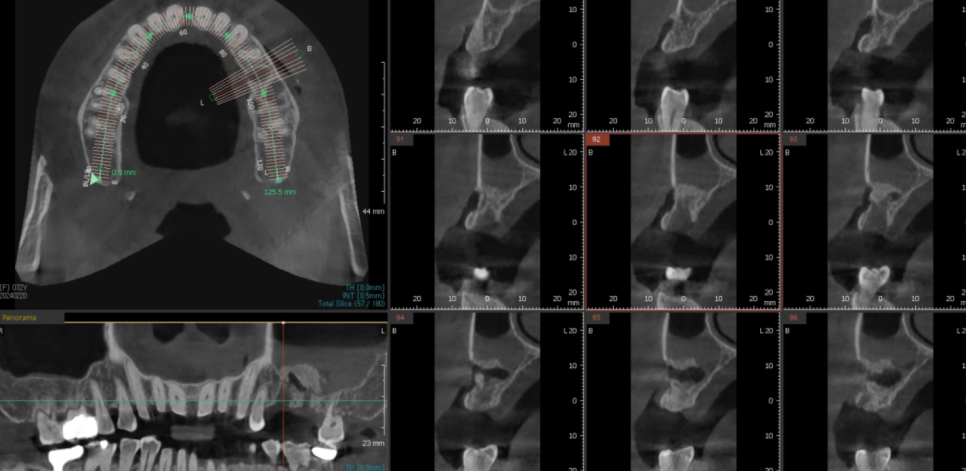

임플란트를 위해 ct 촬영을 시행했습니다.

진단 결과 남아있는 뼈의 두께도 얇고

치아 뼈 폭도 좁아서 Lateral 방법으로 진행하기로 상담 드렸습니다.

24.02.20

수술 후 사진입니다.

상악동을 올리면서 뼈이식을 진행하여

돔 형태로 잘 만들어진 것이 확인됩니다.